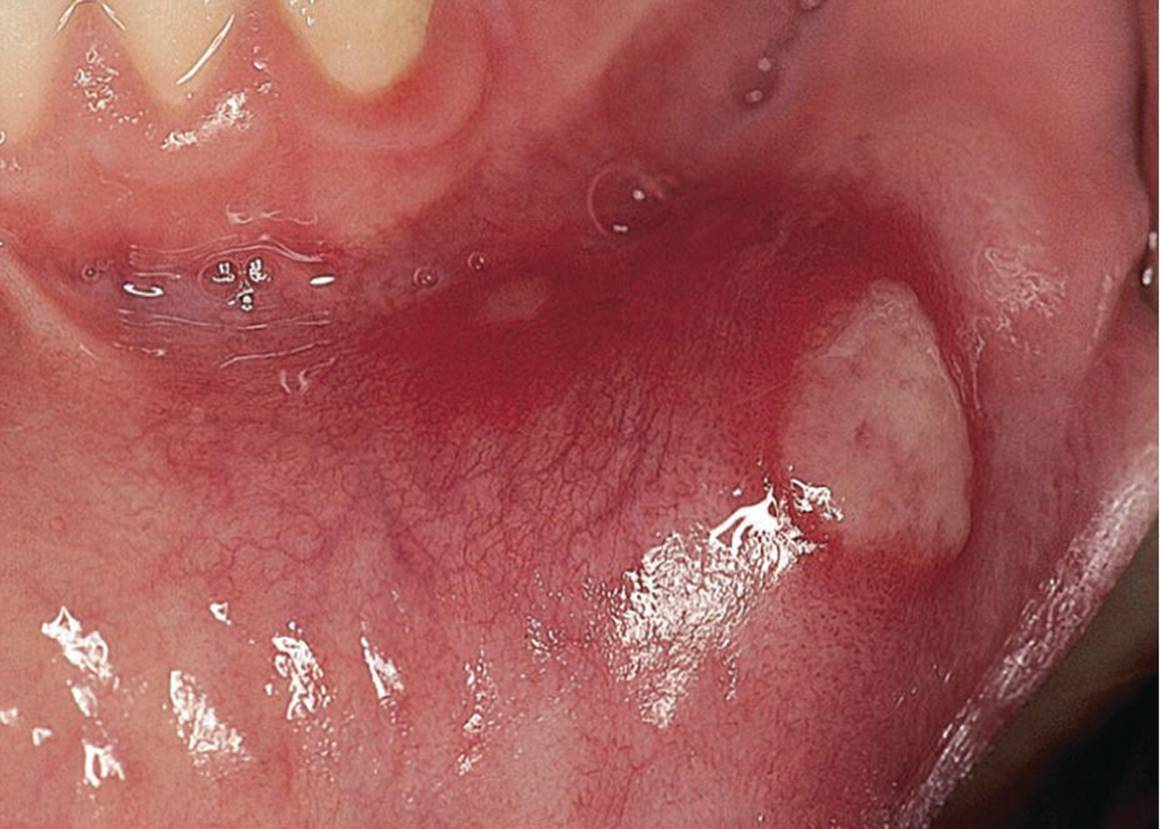

Ranula is essentially a large mucocele, located as a bluish swelling of the floor of the mouth (Figure 15.18). It arises from the salivary glands in that region. Due to extravasation or retention of mucus from excretory ducts of sublingual glands caused by trauma or infection, the extensive translucent swelling may occur.

Figure 15.18 Ranula located in the floor of the mouth.